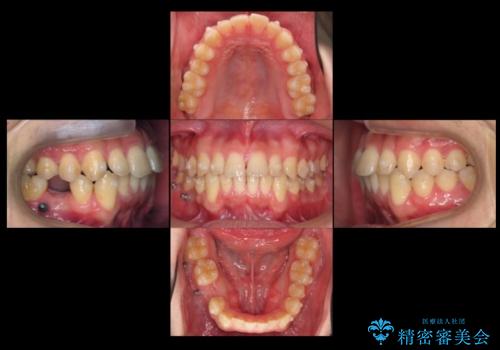

右下に乳歯が残っていましたが、後に続く永久歯がありませんでした。

乳歯も根が吸収しており長くは持たない状況でしたので、まず乳歯を抜歯し、他の歯を矯正治療で歯を並べてからインプラントで補綴しました。

先にインプラントをしてしまうと、矯正治療で周りの歯を動かす事ができなくなってしまいます。

矯正治療→インプラントの順で行います。